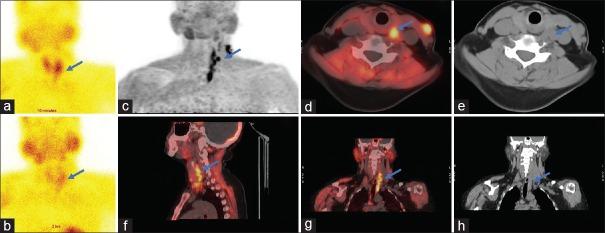

Parathyroid carcinoma (PTC) is a rare endocrine tumor and uncommon cause for primary hyperparathyroidism. F-fluorocholine (FCH) positron emission tomography and computed tomography (PET/CT) has shown promising results in the detection of parathyroid adenoma, though its role in PTC is undefined due to the paucity of incidence. The authors in this case report discuss the possible complimentary role of FCH PET/CT with F-fluorodeoxyglucose PET/CT in the evaluation of the management of suspected recurrence, since this rare entity has high loco-regional and distant recurrence of the disease.

甲状旁腺癌(PTC)是一种罕见的内分泌肿瘤,也是原发性甲状旁腺功能亢进的不常见病因。F-氟胆碱(FCH)正电子发射断层扫描和计算机断层扫描(PET/CT)在甲状旁腺腺瘤的检测中已显示出有前景的结果,不过由于其发病率低,FCH PET/CT在PTC中的作用尚不明确。该病例报告的作者讨论了FCH PET/CT与F-氟脱氧葡萄糖PET/CT在评估疑似复发的处理中可能具有的互补作用,因为这种罕见疾病具有较高的局部区域和远处复发率。